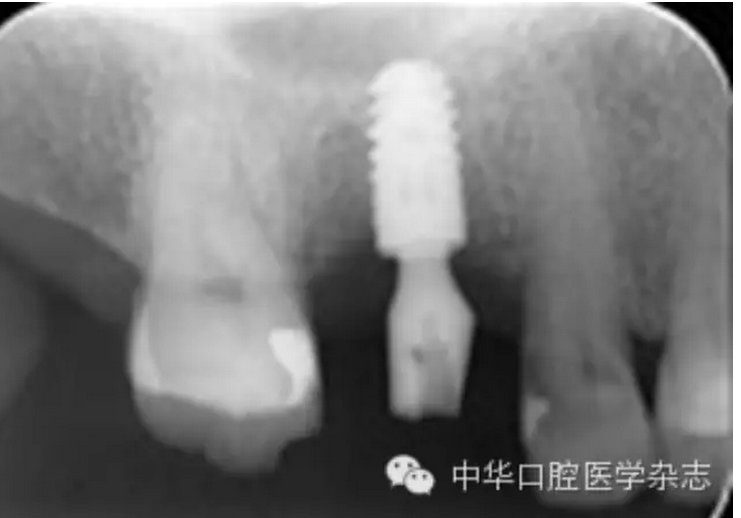

平臺(tái)轉(zhuǎn)換種植修復(fù)基臺(tái)折斷六例原因分析

【摘要】目的 分析平臺(tái)轉(zhuǎn)換種植修復(fù)基臺(tái)折斷原因,探討處理辦法及預(yù)防策略。方法 2001年1月至2014年12月植入的平臺(tái)轉(zhuǎn)換種植體2 487枚中,2009年3月至2014年2月發(fā)生平臺(tái)轉(zhuǎn)換種植修復(fù)基臺(tái)折斷6例,男性5例、女性1例,平均年齡63歲(55~78歲),均使用Ankylos®種植系統(tǒng),6例均為修復(fù)完成2~8年后發(fā)生修復(fù)基臺(tái)折斷。分析修復(fù)基臺(tái)折斷與力及其連接方式等因素的關(guān)系。結(jié)果 基臺(tái)折斷率為0.24%(6/2 487)。6例折斷基臺(tái)均發(fā)生在磨牙區(qū)、牙冠面均為貴金屬。6例折斷基臺(tái)均無(wú)法完整取出,最終取出種植體后重新種植修復(fù)。結(jié)論 平臺(tái)轉(zhuǎn)換種植修復(fù)基臺(tái)折斷后取出困難,應(yīng)注重預(yù)防此嚴(yán)重并發(fā)癥。磨牙區(qū)種植修復(fù)應(yīng)謹(jǐn)慎使用平臺(tái)轉(zhuǎn)換種植系統(tǒng);通過(guò)增加種植體數(shù)量、采取烤瓷聯(lián)冠修復(fù)可能降低基臺(tái)折斷風(fēng)險(xiǎn)。使用小直徑、短種植體可減少取出種植體時(shí)的創(chuàng)傷,有利于再次種植。

轉(zhuǎn):中華口腔醫(yī)學(xué)雜志